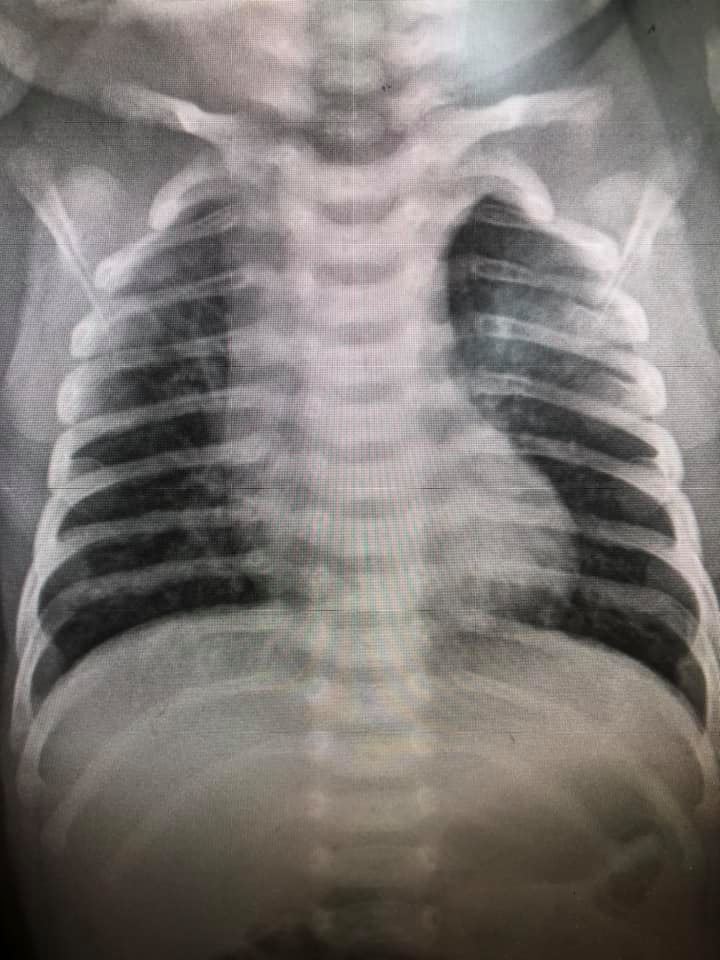

ล่าสุด วันที่ 6 พฤศจิกายน 2563 เฟซบุ๊ก Infectious ง่ายนิดเดียว ได้โพสต์ภาพฟิล์มเอกซเรย์ปอดเด็กที่ติดเชื้อไวรัส RSV 10 คน ที่เข้ารับการรักษาที่โรงพยาบาล โดยได้รับการวินิจฉัยว่ามีอาการหลอดลมอักเสบ ปอดอักเสบ โดยฝ้าสีขาวคือตำแหน่งทีติดเชื้อ สีดำคือปอดปกติ พร้อมระบุข้อเท็จจริงของ RSV ดังนี้